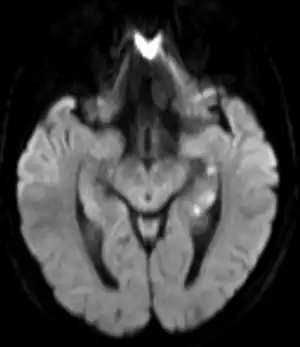

![]() | |

| Abnormal hippocampus findings consistent with transient global amnesia on MRI | |